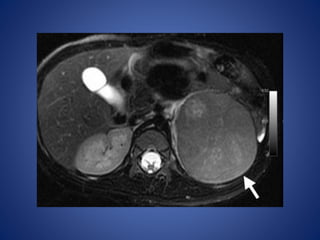

At MR imaging, the solid portion of the tumor demonstrates intermediate signal

intensity with multiple hyperintense cystic spaces on T2-weighted images,

creating a spongelike appearance

At MR imaging,the solid portion of the tumor demonstrates intermediate signal intensity with multiple hyperintense cystic spaces on T2-weighted images, creating a spongelike appearance